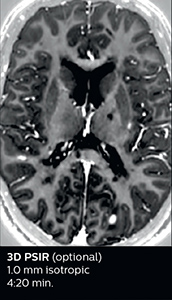

The abbreviated MS protocol for brain is only around 9 minutes, so in case of suspected multiple sclerosis, one or two more advanced sequences may be added, such as PSIR (phase sensitive inversion recovery) or susceptibility-weighted sequences to help us make more confident diagnoses in these inflammatory cases.

In this example, the optional 3D multishot susceptibility weighted sequence with 0.6 mm isotropic voxels is 2 lesions with a central vein sign (arrows) and one lesion with a phase-rim sign (arrowhead). The total scan time, including SmartBrain and axial PD/T2 3mm, is 11:10 min. and is 18:30 min. with the optional 3D PSIR and 3D SWI multishot included.